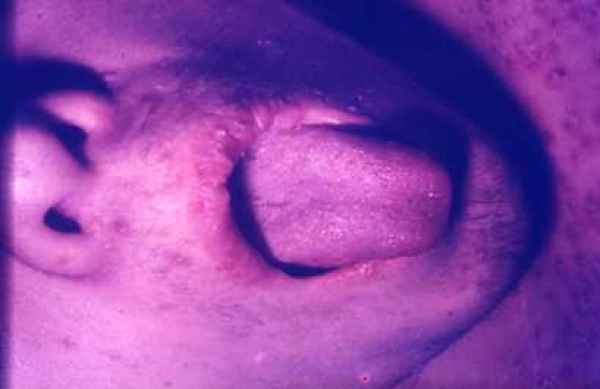

Alteraciones de la piel y tegumentos